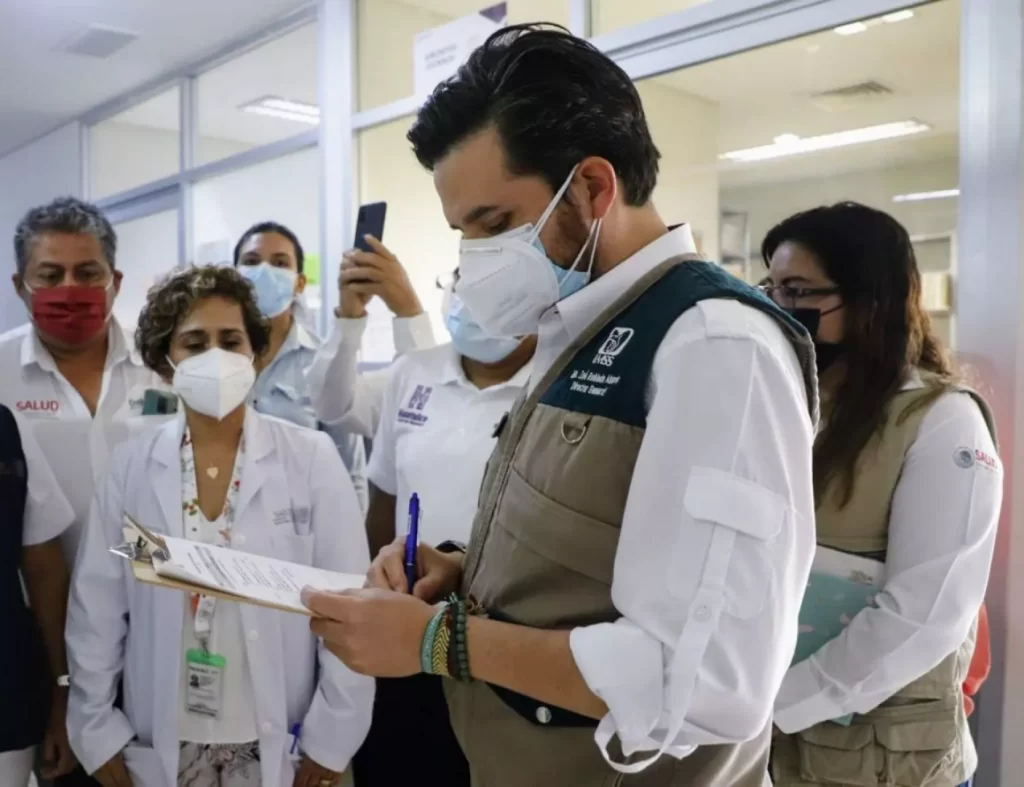

Pacientes del IMSS en Tapachula deben arrodillarse para hacer trámites; la institución revisa las ventanillas

Imágenes y videos difundidos en redes sociales el jueves 28 de mayo muestran a pacientes del Hospital General de Zona No. 1 «Nueva Frontera» del IMSS en Tapachula, Chiapas, arrodillados en el piso para poder comunicarse con el personal administrativo, entregar documentos y firmar de recibido a través de ventanillas de trámites construidas a una […]

El reto de cuidar los riñones en México: la enfermedad renal pone en alerta al IMSS

Más de dos millones de personas afiliadas enfrentan algún grado de daño renal, mientras especialistas insisten en la urgencia de adoptar hábitos saludables para proteger estos órganos vitales Más de 2.3 millones de personas afiliadas al IMSS viven actualmente con algún grado de enfermedad renal, según datos institucionales. De ese universo, 85 mil requieren ya terapias sustitutivas como diálisis […]